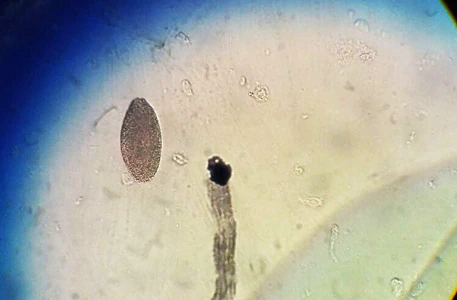

A patient, who lives in a rural region in South America, presented with bloody diarrhea and remembers having eaten undercooked pork. The attending physician submitted images to the DPDx Team of a roundworm he observed during a colonoscopy. Based on the inner structures observed which appeared to be stichocytes, Trichinella spp. was initially suspected as the causative agent. However, an ELISA test for trichinellosis was negative. Figures A–C show what was observed from the colonoscopy. What is your diagnosis? Based on what criteria?

Figure A